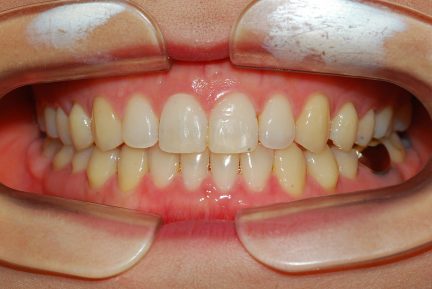

Classe III, articulé postérieur, arcades étroites, arcades asymétriques, déviation de la ligne médiane mandibulaire, décalage de la ligne médiane, rotations, espacement

- Relation de classe I obtenue

- Guidage fonctionnel des canines des deux côtés

- Articulé antérieur corrigé

- Articulé postérieur corrigé

- Surplomb et recouvrement normaux obtenus

- Lignes médianes coïncidentes

- Alignement des deux arcades par dérotation

- Forme de l'arcade améliorée

État initial